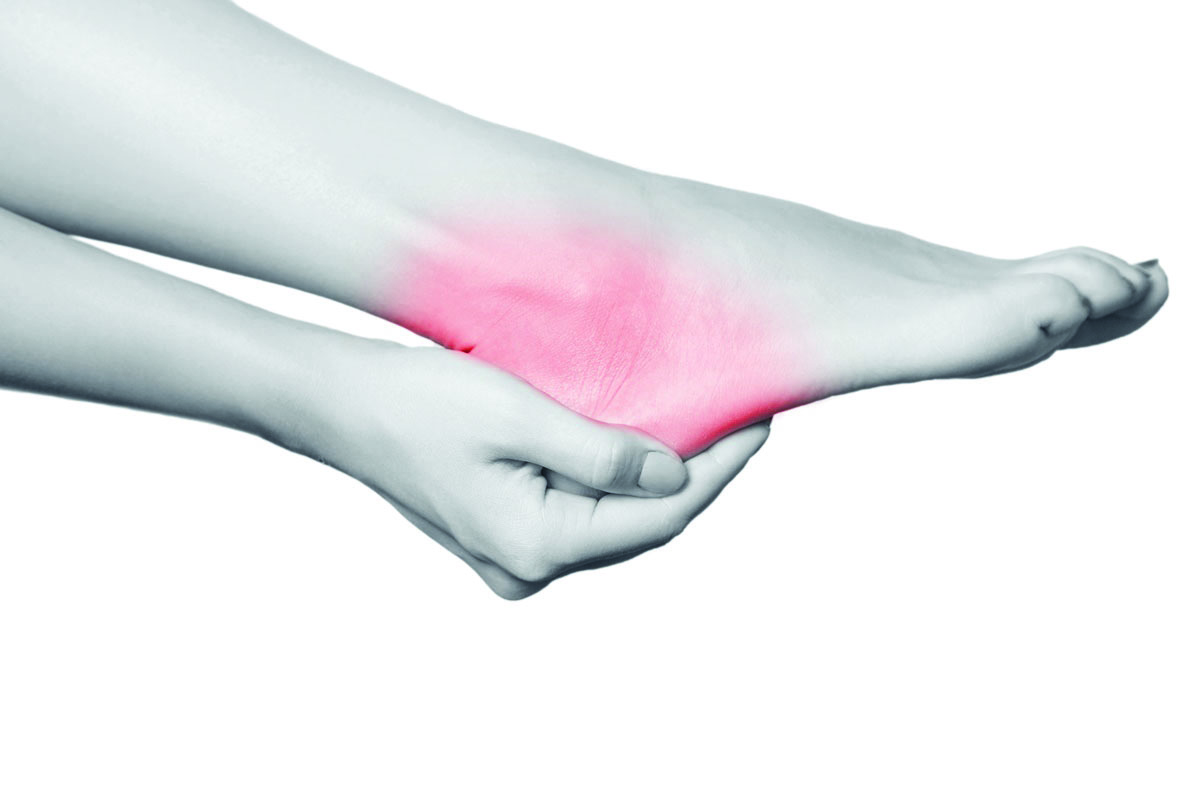

Esporão de calcâneo: esforço excessivo pode causar inflamações e fissuras

Inflamação crônica e microtraumatismo no osso calcâneo – o maior da estrutura óssea do pé responsável por suportar todo o peso do corpo e sofrer impactos intensos e constantes – podem resultar na formação do esporão. A doença degenerativa atinge a parte de baixo ou a região posterior desse osso do calcanhar e é caracterizada por uma protuberância óssea ou um crescimento anormal na sola do pé.

Outros fatores de risco estão relacionados à idade (acima de 40 anos), obesidade e sobrepeso, pés cavos (curvatura acentuada) ou chatos (planos), alterações na marcha, má postura, calçados inadequados, permanecer muitas horas de pé e atividades físicas de alta colisão. As doenças como fascite plantar, artrite reumatoide, osteoartrite e gota também contribuem para o desenvolvimento do esporão de calcâneo.

O médico ortopedista e traumatologista, Joaquim Reichmann, explica que existem dois tipos de esporão: o inferior, que compromete a fáscia plantar e o posterior, da bolsa retrocalcânea, localizada na parte inferior dos pés. O ósseo calcâneo está conectado a diversos tendões, ligamentos e à fáscia plantar – que é uma membrana de tecido fibroso que se estende do osso do calcanhar até os dedos dos pés, responsável por amortecer e distribuir o impacto. O tendão de Aquiles estabelece a conexão entre o osso calcâneo e os músculos da panturrilha.

Segundo Reichmann, a dor é o principal sintoma do esporão do calcâneo. Normalmente, é sentida de maneira pulsante na região plantar do calcanhar. O incômodo surge ao colocar o sapato e após a prática de esportes. “Nem todas as dores no calcanhar, no entanto, são sinais de esporão. Por isso, é necessário realizar exames físicos e de imagens, como radiografia e ressonância magnética para diagnosticar a patologia”, comenta.

O tratamento consiste no alívio da dor e no controle do processo inflamatório. Entre as indicações, de acordo com o médico, estão fisioterapia, exercícios de alongamento, massagens, analgésicos, repouso, compressas de gelo, elevação do membro comprometido, uso de palmilhas ortopédicas de silicone sob o calcanhar e terapia por ondas de choque (ultrassom). Quando o paciente não responder ao tratamento conservador, a orientação é realizar infiltração de corticoides no local. A cirurgia é recomendada nos quadros graves que requerem a remoção do esporão.